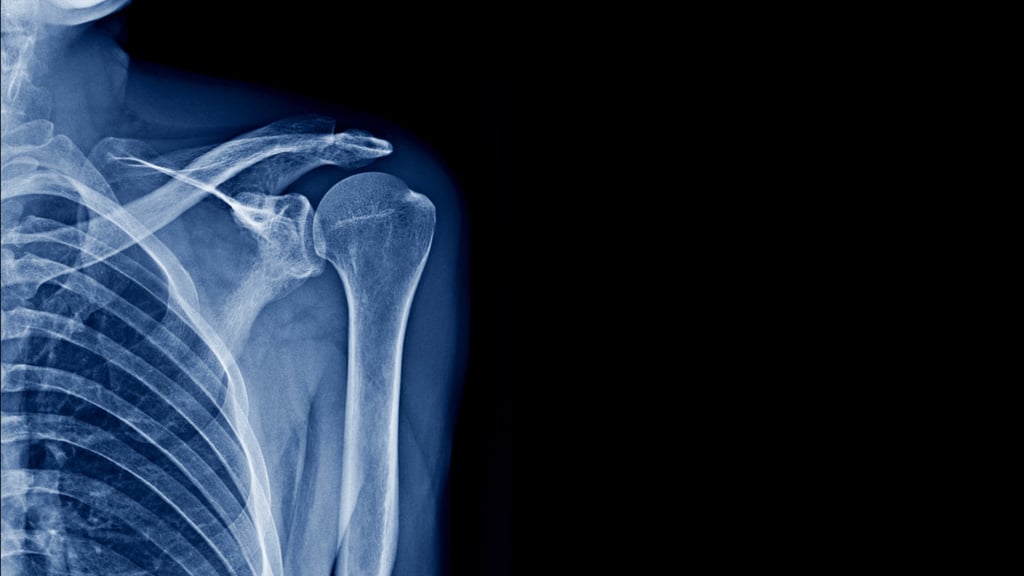

Χειρουργική Άνω Άκρου

Η χειρουργική αποκατάσταση του άνω άκρου περιλαμβάνει την αντιμετώπιση καταγμάτων, αρθρώσεων και παθήσεων με στόχο την πλήρη αποκατάσταση της λειτουργικότητας και την επιστροφή σε καθημερινές δραστηριότητες.